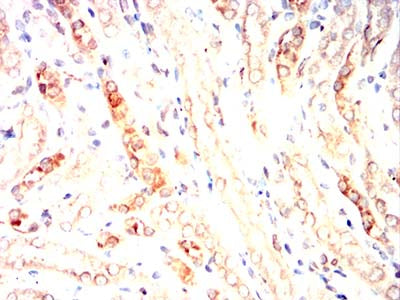

Immunohistochemical analysis of paraffin-embedded breast cancer tissues using MRP3 mouse mAb with DAB staining.